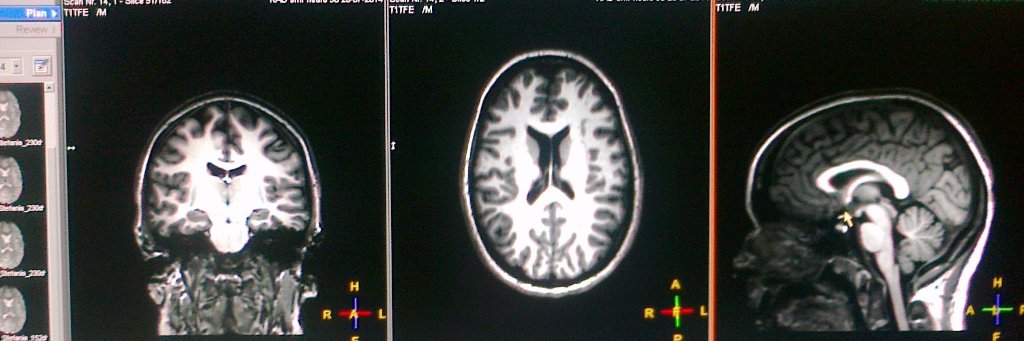

New from the lab! And 50 day free access here authors.elsevier.com/c/1iqFa2VHYC4IA – On the association between white matter and precursors of math and reading in 5-year-olds before the start of formal schooling (1/8)

Thanks to @InnovationCA funding, Stephanie Bugden, Amy Desroches, and Stephen Smith have opened the Centre for Cognitive Neuroscience. Their research will examine the neural mechanisms underlying children’s ability to learn, read, write, and perform math.news.uwinnipeg.ca/new-cutting-ed…